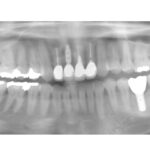

多数の欠損がある場合、どのような治療方法が考えられるのか?

上顎前歯部が1歯欠損した場合のインプラント治療

骨吸収が大きくインプラント治療が困難なケースに対して、 どのような治療法 や 選…

どこまでインプラント治療を行うのか?

インプラント追加長期症例

多くの歯がない場合の治療の進め方

ソケットリフト法を併用したインプラント治療

最もインプラント治療に適している症例

奥歯が欠損した場合の治療法:義歯、ブリッジ、インプラント